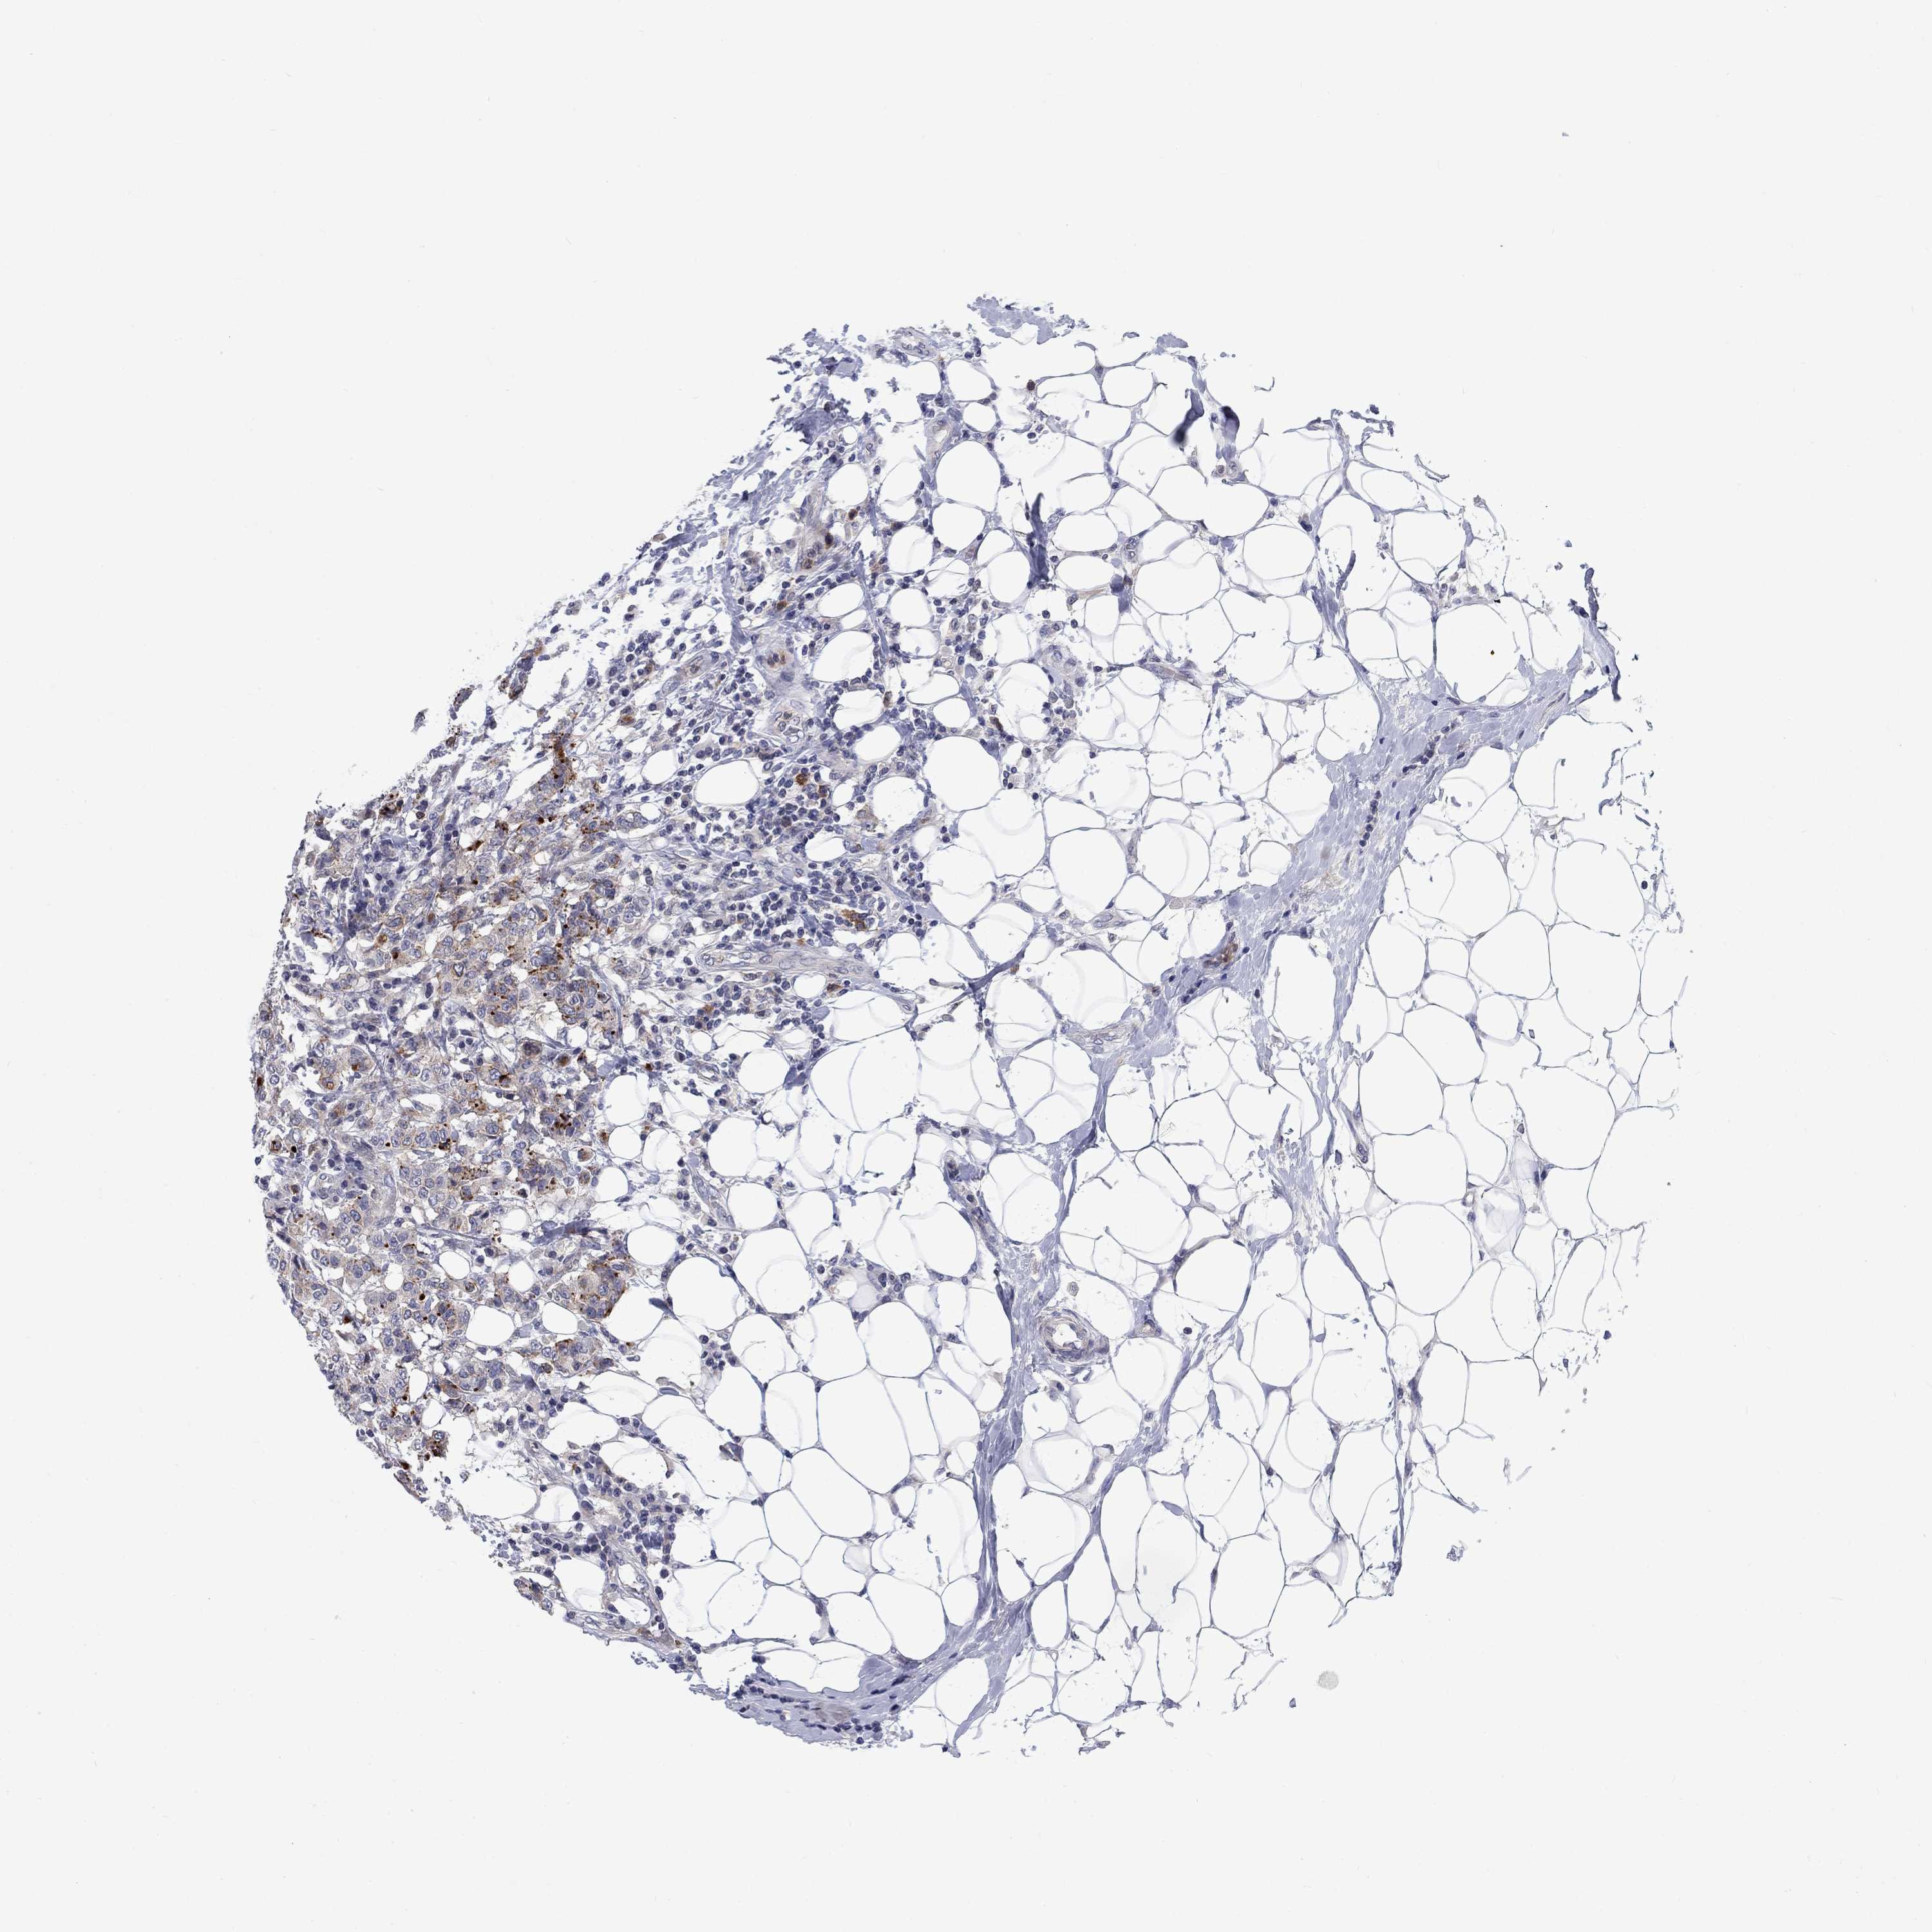

BRCA TCGA BRCA VALIDATION PROTEIN EXPRESSION